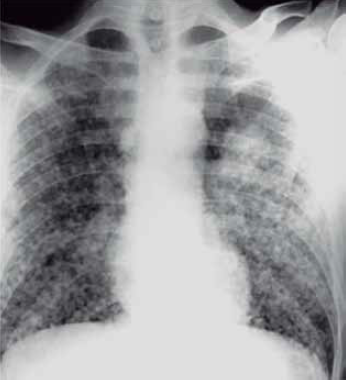

Homem de 59 anos, tabagista de longa data, desempregado e sem exposição ocupacional, é internado com quadro de tosse e dispneia progressiva. Ele não está bem há algum tempo e recebeu vários cursos de antibióticos para “bronquite”. Nos últimos 4 meses não teve acompanhamento médico, e perdeu cerca de 12% do peso corporal. Ao exame físico: queda do estado geral; afebril; roncos e crepitações difusas (tipo velcro). A gasometria arterial mostra PO2 de 68 mmHg com alcalose respiratória compensada leve. O escarro é negativo para tuberculose. A radiografia de tórax é mostrada a seguir.

(Arquivo pessoal; imagem usada com autorização)